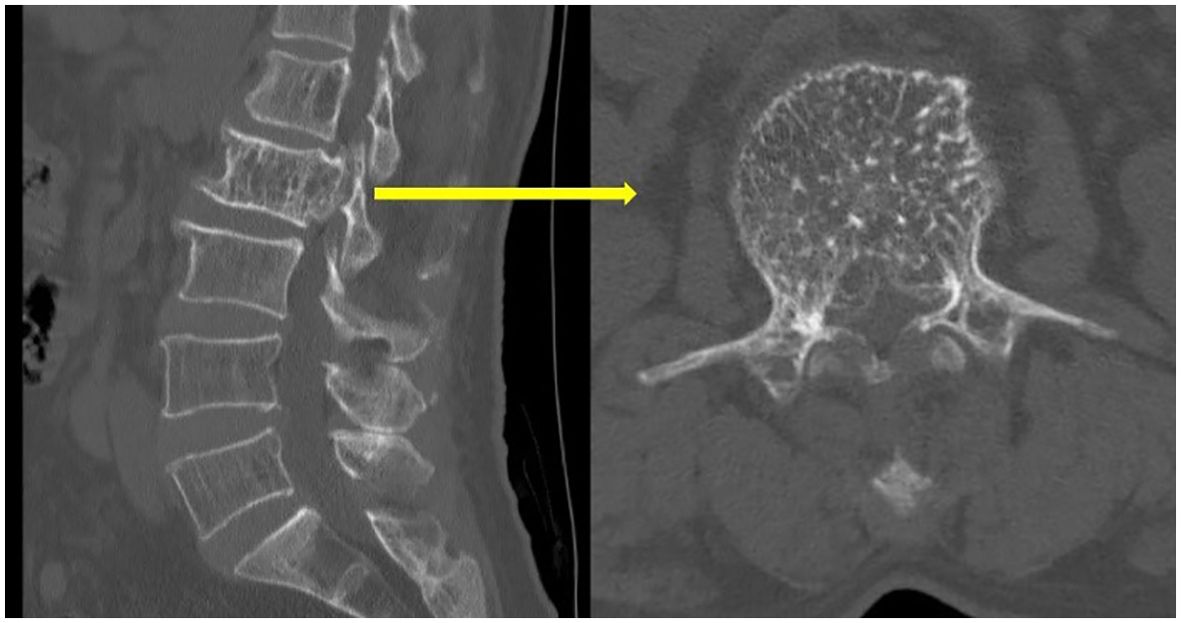

Upon physical examination, tenderness and percussion pain were observed in the L1 and L2 spinous processes, with radiating pain in both lower limbs. Bilateral iliopsoas muscle strength was graded as IV. The strength of the other muscle groups remained normal. The lumbar extension test was positive, and bilateral Babinski signs were negative. The mean preoperative visual analog scale (VAS) was 8. Preoperative lumbar CT revealed a mass with abnormal density in the L2 vertebral body and posterior elements, with vertebral body deformation and spinal stenosis, and within the L1 vertebral body and left posterior elements (Figure 1). Preoperative lumbar MRI revealed patchy T1 hypointensity and T2 hyperintensity on the left side of the L1 vertebral body and posterior elements, with high signal on fat-suppressed sequences. The L2 vertebral body was slightly flattened, with posterior bulging of the vertebral body margin. The vertebral body and bilateral posterior elements demonstrated T1 hypointensity and T2 hyperintensity, with high signal on fat-suppressed sequences, and the corresponding spinal canal was significantly compressed, narrowed, and deformed. Heterogeneous signals were observed within the spinal canal at the L1-L2 level, with compression and displacement of the cauda equina (Figure 2). Preoperative lower-limb electromyography was performed to further quantify the degree of bilateral lower extremity neurological dysfunction and to assist in differential diagnosis. The results revealed reduced motor conduction wave amplitude of the bilateral common peroneal nerves, a lack of definite waveforms induced by the right common peroneal nerve F-wave, and abnormal spontaneous electrical activity in the bilateral gastrocnemii, right tibialis anterior, and tibialis posterior muscles, with partial widening of the Motor Unit Potential duration in the right tibialis posterior muscle. The preoperative diagnosis was AVH at L1 and L2 (Enneking stage 3).

Figure 1. Preoperative lumbar CT revealed honeycomb and fence-like changes.